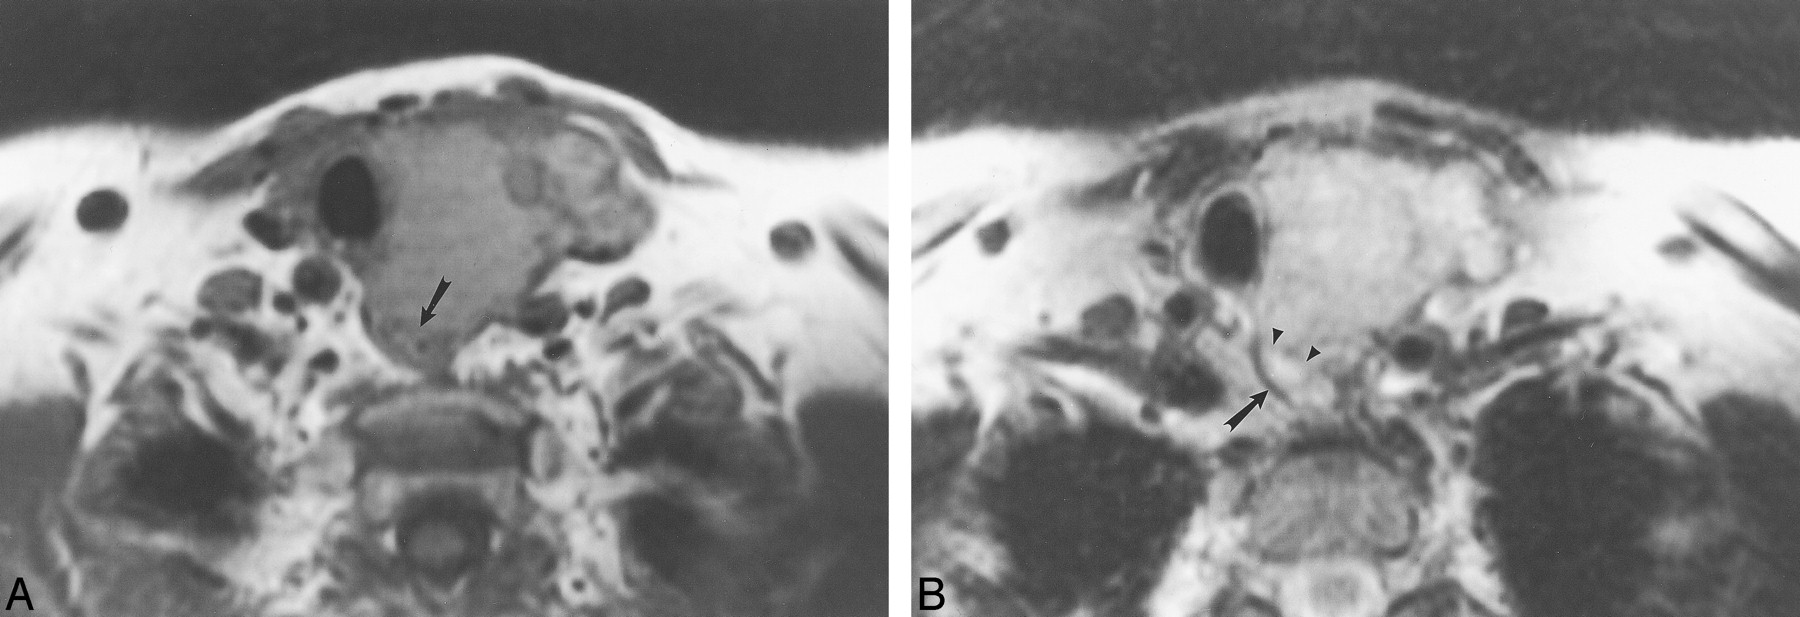

This 62-year-old man with metastatic laryngeal carcinoma to cervical lymph nodes had surgically proven esophageal invasion.

A, Axial T1-weighted image (700/17) shows obliteration of the fat plane between the mass (arrowheads) and the right lateral esophageal wall. There is focal wall thickening of the esophagus (white arrow). The esophageal lumen is distended with air (black arrow). The mass abuts the esophageal wall for less than 180o.

B, Axial T2-weighted image (4000/80) demonstrates increased esophageal wall signal (arrow) adjacent to the mass.

C, Axial enhanced 3D FMPSPGR image (235/21; flip angle, 90o) shows increased enhancement of the esophageal wall (arrow) as well as diffuse enhancement of the adjacent mass.